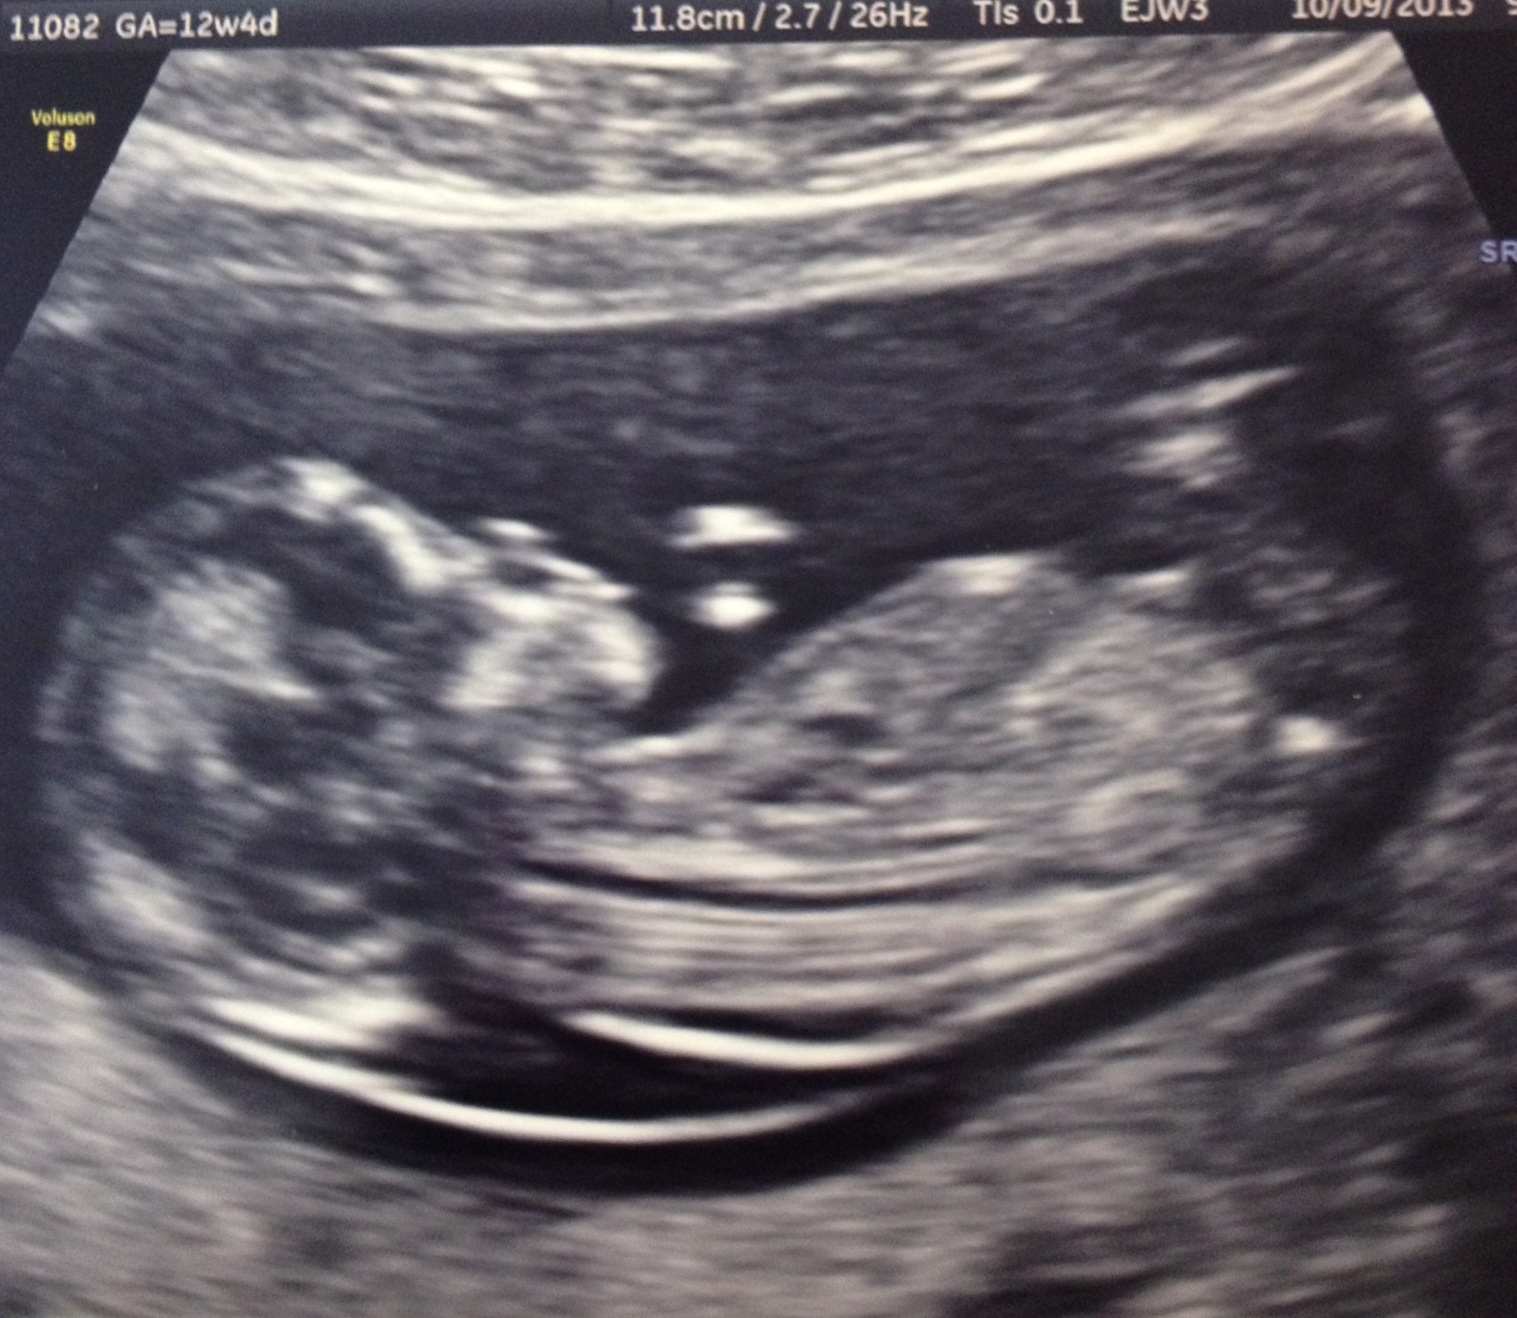

Can anyone see anything in this u/s pic??

Can anyone see a nub on this pic???